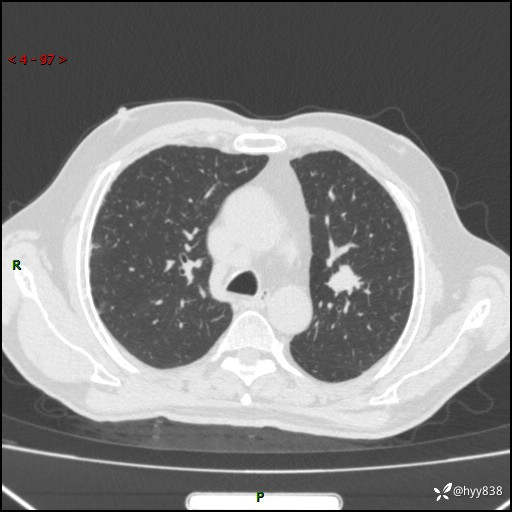

简要病史:患者4月前无明显诱因后背正中间疼痛,间断阵痛,无低热、咳嗽,盗汗、咯血、胸痛、喘气等不适,2024-2-25当地第二人民医院胸部CT提示“1.双肺感染病变;2.左肺上叶及右肺中叶结节灶;3.双肺肺气肿并肺大泡4.纵膈淋巴结肿大5.主动脉及冠脉硬化,今为求明显结节性质遂来我院门诊就诊,门诊以“肺占位”收治入院。 起病以来,患者精神饮食睡眠一般,大小便正常,体力体重无明细变化。

辅助检查:CT

临床诊断:肺占位

胸部CT平扫